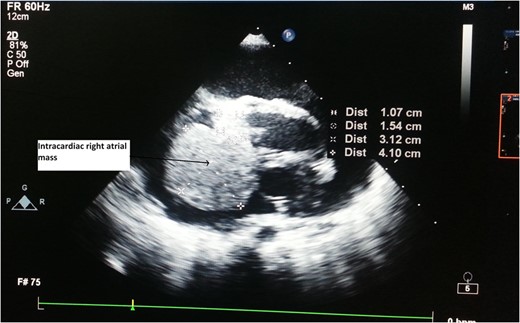

A 2-year-old male child was brought to hospital with respiratory distress since last 2 weeks. He was having repeated respiratory tract infection since last 3 months along with poor oral intake and poor activity. His symptoms progressed from New York Heart Association (NYHA) Functional Class II to IV over last 2 weeks. On investigation at another hospital he was diagnosed with intracardiac mass having extracardiac extension. Parents brought the child to our hospital for further management.

CT Thorax showing intracardiac right atrial mass with extracardiac extension.